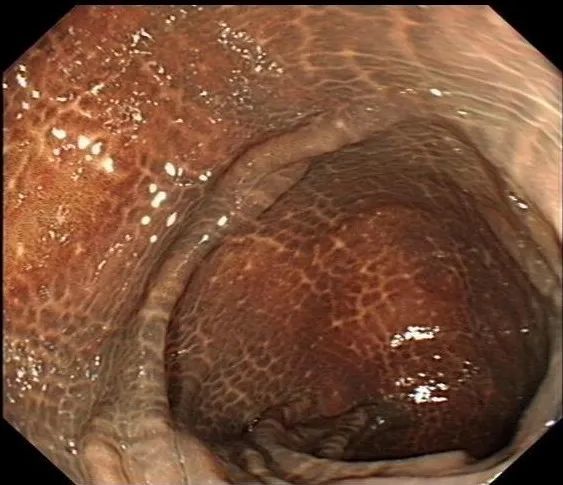

文中提到作者的肠子变黑了 , 用医学术语讲 , 应该是“结肠黑变”或“结肠色素沉着” , 就像肠粘膜上长了“老年斑” 。 肠镜下 , 正常的结肠粘膜是淡红色的 , 表面光滑平坦 , 可以见到清晰的血管纹理 。 结肠黑变的粘膜呈现深浅不等的褐色 , 甚至是黑色 , 有像豹纹、蛇皮一样的斑纹 。

文章插图

【减肥|花式“粪斗”八年,终获“花花肠子”一副】

正常肠粘膜、黑变的肠粘膜(密恐者谨慎左滑)丨段卓洋供图